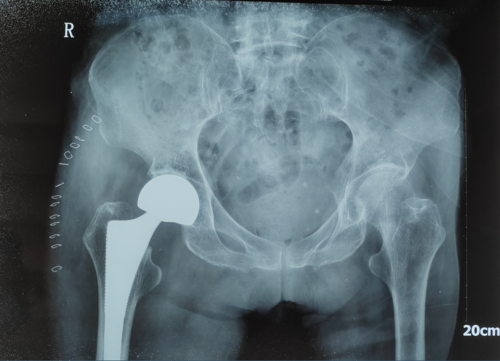

同时着急的还有我们医务人员啊,面对百岁老人股骨颈骨折,我们医务人员心里也犯嘀咕啊,这么大年纪的股骨颈骨折,都已经破我院股骨颈骨折患者年龄最高纪录了,当即我们便开通了绿色通道,立即开展一系列对症治疗、全面检查,立马组织内科、麻醉科会诊,商定手术方案,最后取得卢老太及其子女一致同意后,拟行人工股骨头置换术,术前准备一切都在有条不紊的进行,就在术前当晚,患者出现发热,这可把我们医务人员愁坏了,原则上关节置换术前三天不允许出现发热(容易导致关节内感染),但是高龄患者卧床时间久了很容易出现肺炎、褥疮、谵妄等并发症,一旦出现并发症又将延误最佳手术时机,在取得患者及其家属一致同意后,经过我们医疗团队共同协商决定于2021年07月20日给予卢老太行人工股骨头置换术。一切按照原定剧情似的上演,由我们天使小姐姐护送百岁老人进入手术室、交接、开始麻醉。